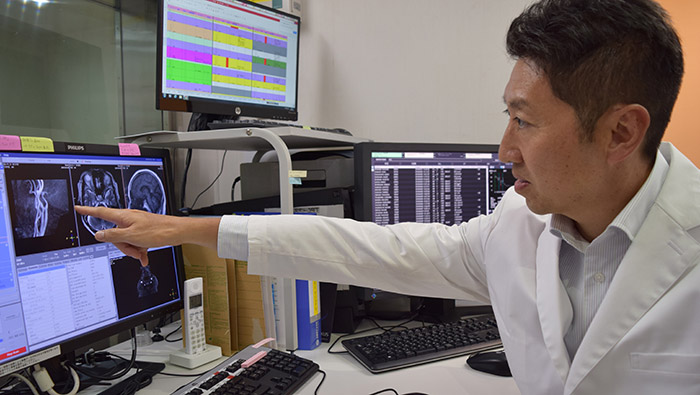

Hideki Koyasu, MD Neurosurgical Clinic in Kanagawa, Japan.

Neurosurgeon and Director of KOYASU

Dr. Koyasu points out the key strength of Compressed SENSE. “It significantly speeds up our scanning, and in my perception, we obtain the same image quality as before without Compressed SENSE.”

According to Dr. Koyasu, the acceleration provided by Compressed SENSE is accompanied by some additional benefits. “Compressed SENSE helps us to reduce the time that a patient needs to lie still in the magnet bore. This is nice for patients and can also benefit image quality, as in general the occurrence of motion artifacts tends to be worse in longer scans,” he says.

“We now only need about 10 minutes of scan time for a brain exam – and we still get the same amount of images and equal quality. We even managed to make a very useful improvement: we replaced the 43-second T21 FFE by a 43-second SWIp, which is more powerful for us in making confident diagnoses in certain patients.” “SWIp was not previously included in our standard protocol, because of its slightly longer scan time. SWIp provides high resolution 3D susceptibility weighted imaging in the brain, which helps to visualize small deoxygenated blood or calcium deposits. Now, with Compressed SENSE, we can perform 3D SWIp in only 43 seconds, so we have included SWIp instead of the 2D T21 FFE that we used previously. Without adding scan time, we now get SWIp images in every routine brain scan and it helps us increase our diagnostic confidence in certain cases.”